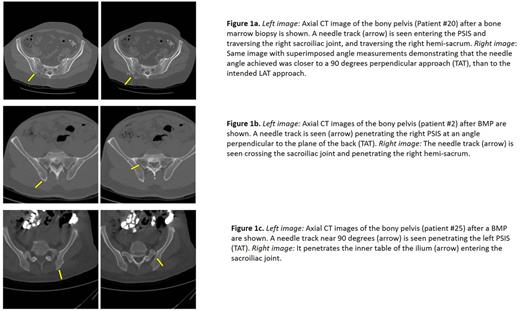

The average age of the 25 patients was 64 years, 44% were female and the average BMI was 25.7. By prespecified criteria, radiographic evidence of needle penetration outside the iliac bone was designated an adverse event. This was observed in 3 of 25 pelvic CT's (12%) where the needle track penetrated the posterior cortex of the ilium, into the sacro-iliac joint and the sacrum (Figures 1a, 1b and 1c). None of the 3 cases had excessive pain or evidence or unusual bleeding, and the pathology of the marrow did not differ between the sacral and the iliac biopsy specimens in terms of length, cellularity or fat content. CT analysis revealed that only a 9 degree deviation from the ASIS target could lead to sacral penetration (figure 1). Needle tracks were detected in the ilium in 5 additional patients. In 17 pelvic CT's, needle tracks were not identified. 2 of 25 patients reported prolonged moderate pain requiring analgesia after the BMP. Needle tracks were not visualized in either patient. No patient developed a significant hematoma or had an unexplained fall in Hb/Hct.

The success and safety of the BMP depend upon correct identification of physical landmarks and correct angulation of the biopsy needle. A cadaver study at this institution showed that biopsy needle angulation towards the ASIS (Lateral Angulation Technique-LAT) was safer than the Traditional Angulation Technique where the needle is directed straight into the PSIS, perpendicular to the plane of the back. The present prospective study of the risks of BMP's by HIT's, supervised by attending investigators, revealed that 8% of the patients had prolonged pain requiring analgesia. Pelvic CT's 5 days after the BMP revealed that 12% of patients had penetration of the sacrum, although none had significant pain or blood loss and the pathology specimen was adequate. Analysis of CT's showed that only a 9 degree change in needle angulation can lead to penetration of the sacrum. We conclude that targeting the ASIS by the LAT approach, avoids inadvertent penetration of the sacrum. The LAT approach is probably safer for patients and may be a new standard of care for hematology training and practice. The high incidence of adverse events (20%) after BMP by HIT's calls for further research and consideration.